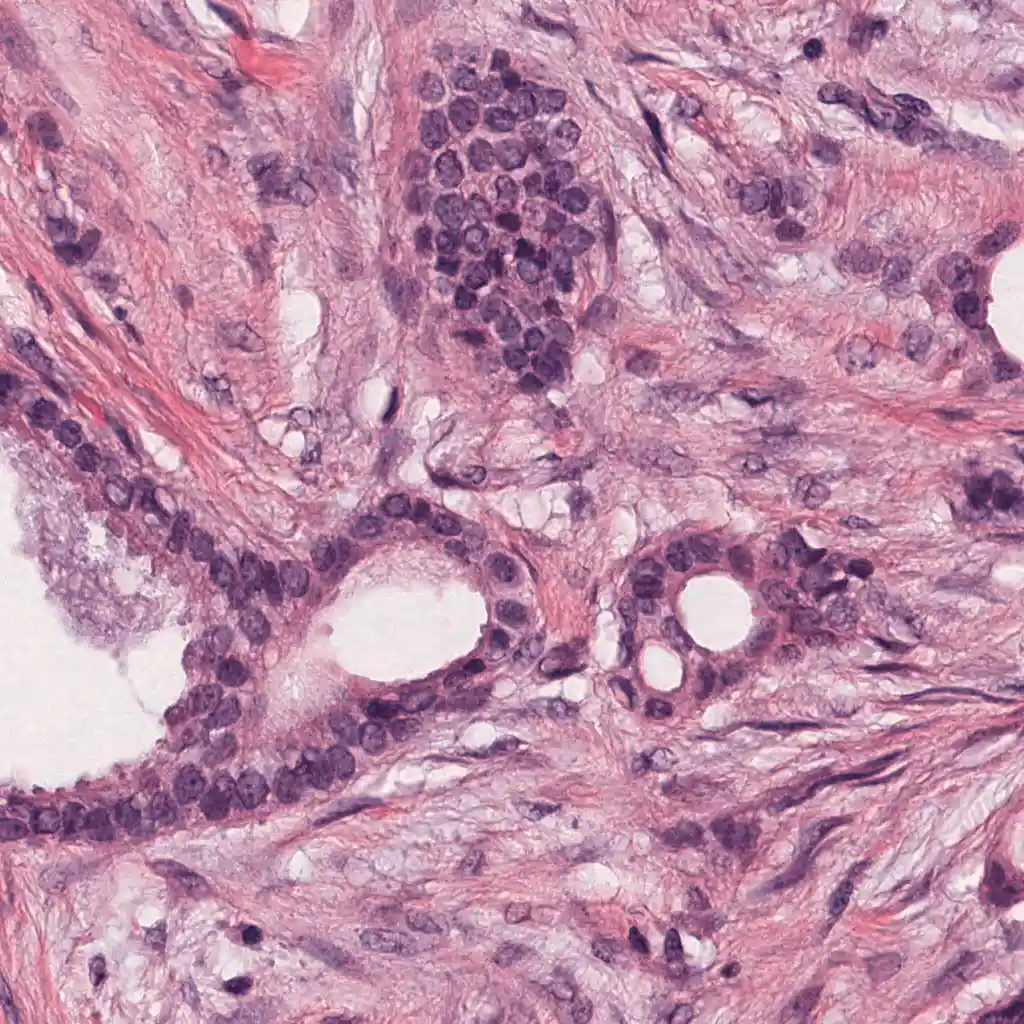

One of the major difficulties in histopathology image analysis is apperance variability. For example, when performing mitosis detection, many false positives can arise when the histopathology slide is overstained. This Python code, adapted from the original MATLAB implementation, performs staining unmixing (separation of the hematoxylin and eosing stains) and apperance normalization. It is based on the method described in [1]. Some examples of staining normalization can be seen in the figure below.